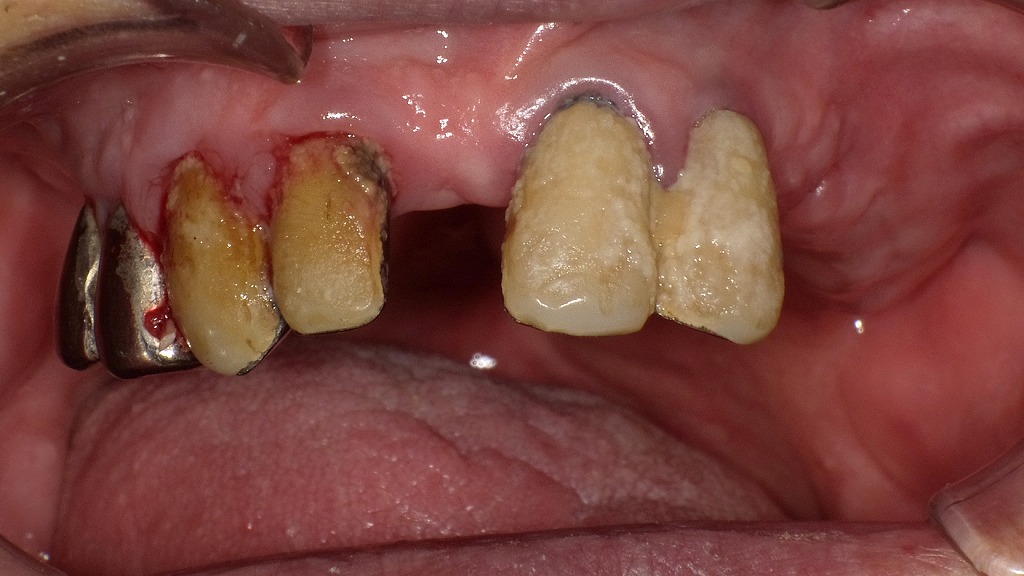

インプラントによる噛む力の回復

歯の欠損を放置すると、噛む力の低下や咀嚼効率の悪化が進み、口腔機能低下症の一因となります。

レントゲン画像の矢印部は、欠損部にインプラントを埋入し、咀嚼機能を回復した症例です。

インプラントは顎の骨に直接固定されるため、しっかり噛める力を取り戻しやすく、食事・発音・嚥下といった口腔機能全体の維持・改善に有効な治療選択肢の一つです。